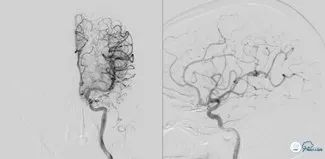

可见基底动脉尖端部血栓,呈次全闭塞状态,前向血流Mtici 2*级A**,无明显前循环向后循环代偿。

图3

图4

图5